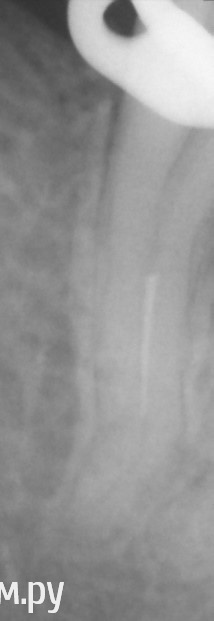

Shaid Опубликовано 16 июня, 2014 Поделиться Опубликовано 16 июня, 2014 Александр, а этот доставабелен?Тоже 2ое посещение мучаюсь. Ссылка на комментарий

Чертков Александр Опубликовано 16 июня, 2014 Поделиться Опубликовано 16 июня, 2014 Александр, а этот доставабелен? Shaid, (извини, не знаю как по имени...не отследил ) на мой взгляд - да, доставабелен, но со скопом. Тут похоже какой то нитинол конусный, а они пружинят и упираются в изгибах, т.е. просто так не "выскочит". А их (изгибов) тут минимум 2... Если изгибы "ровнять" то можно и "ленту" получить по внутренней кривизне, т.к. толщина там небольшая. Ссылка на комментарий

Shaid Опубликовано 16 июня, 2014 Поделиться Опубликовано 16 июня, 2014 Мой инструмент сломался) Профайл 25.04 P.S. Ильдар. Если что Ссылка на комментарий

Shaid Опубликовано 16 июня, 2014 Поделиться Опубликовано 16 июня, 2014 Если со скопом(а это мне, видимо, и предстоит на след.неделе), освободить кончик и долбить УЗ? 1 Ссылка на комментарий

Чертков Александр Опубликовано 17 июня, 2014 Поделиться Опубликовано 17 июня, 2014 Ильдар, да. Постараться максимально "отбайпассить" отломок и УЗ поднимать. Ссылка на комментарий